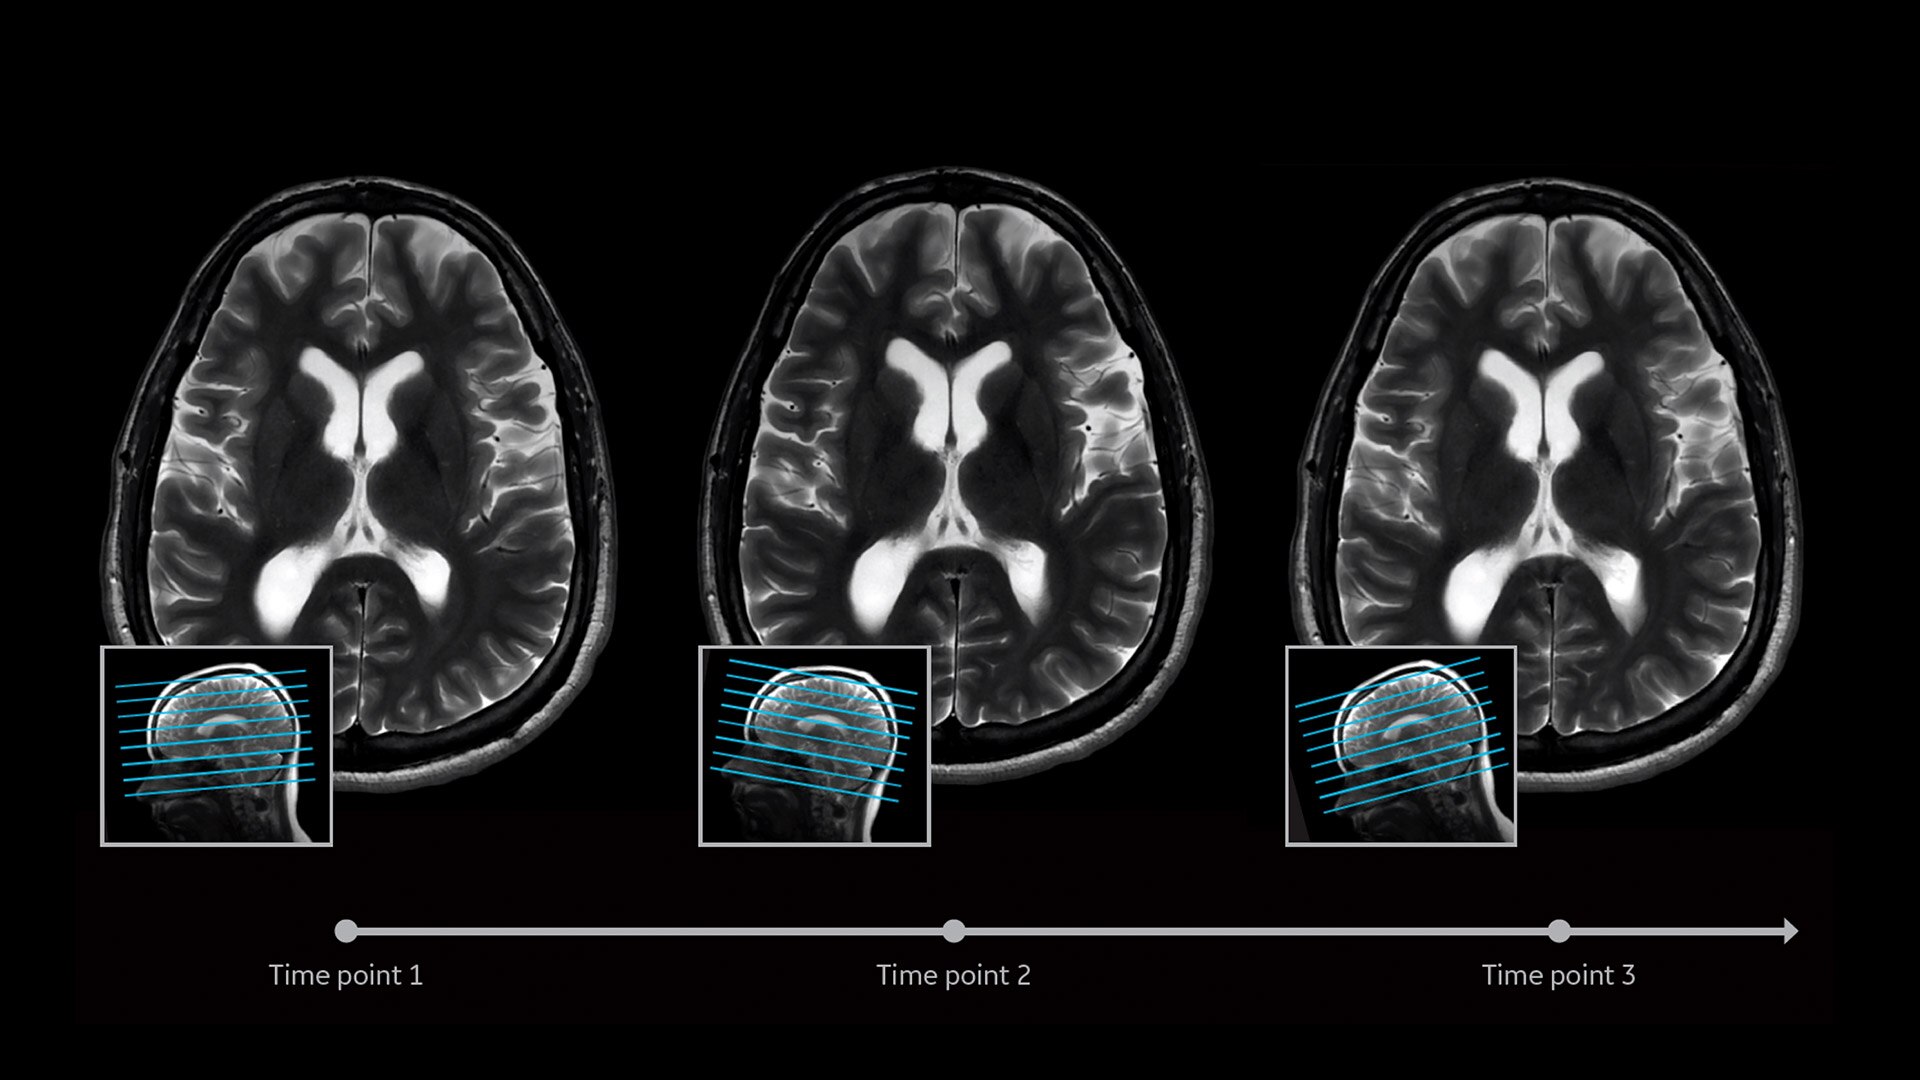

CLARIDAD CON MOTIONFREE BRAIN

El futuro de PET/RM es MotionFree

MotionFree Brain le ofrece gestión del movimiento sin necesidad de marcadores externos, hardware ni tiempo de exploración adicional. Nuestro innovador algoritmo corrige los datos de PET sin procesar de los movimientos reales de la cabeza del paciente. Esto ayuda a proporcionar una mejora significativa en la precisión cuantitativa, especialmente en lesiones cerebrales pequeñas.

Para garantizar una adquisición de imágenes sin movimiento lo más cómoda posible, MotionFree Brain es compatible con todas las funciones de PET/RM de SIGNA™, como Q.Clear y ZTE MRAC.